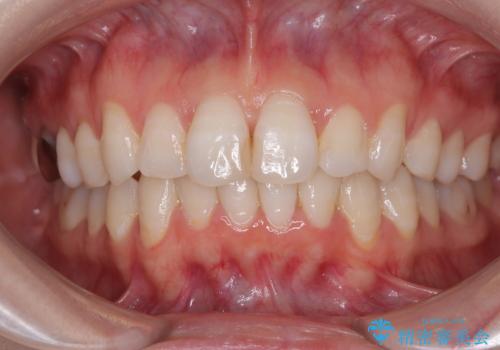

[マルチブラケットで後方移動] ワイヤー矯正で行う噛み合わせの改善